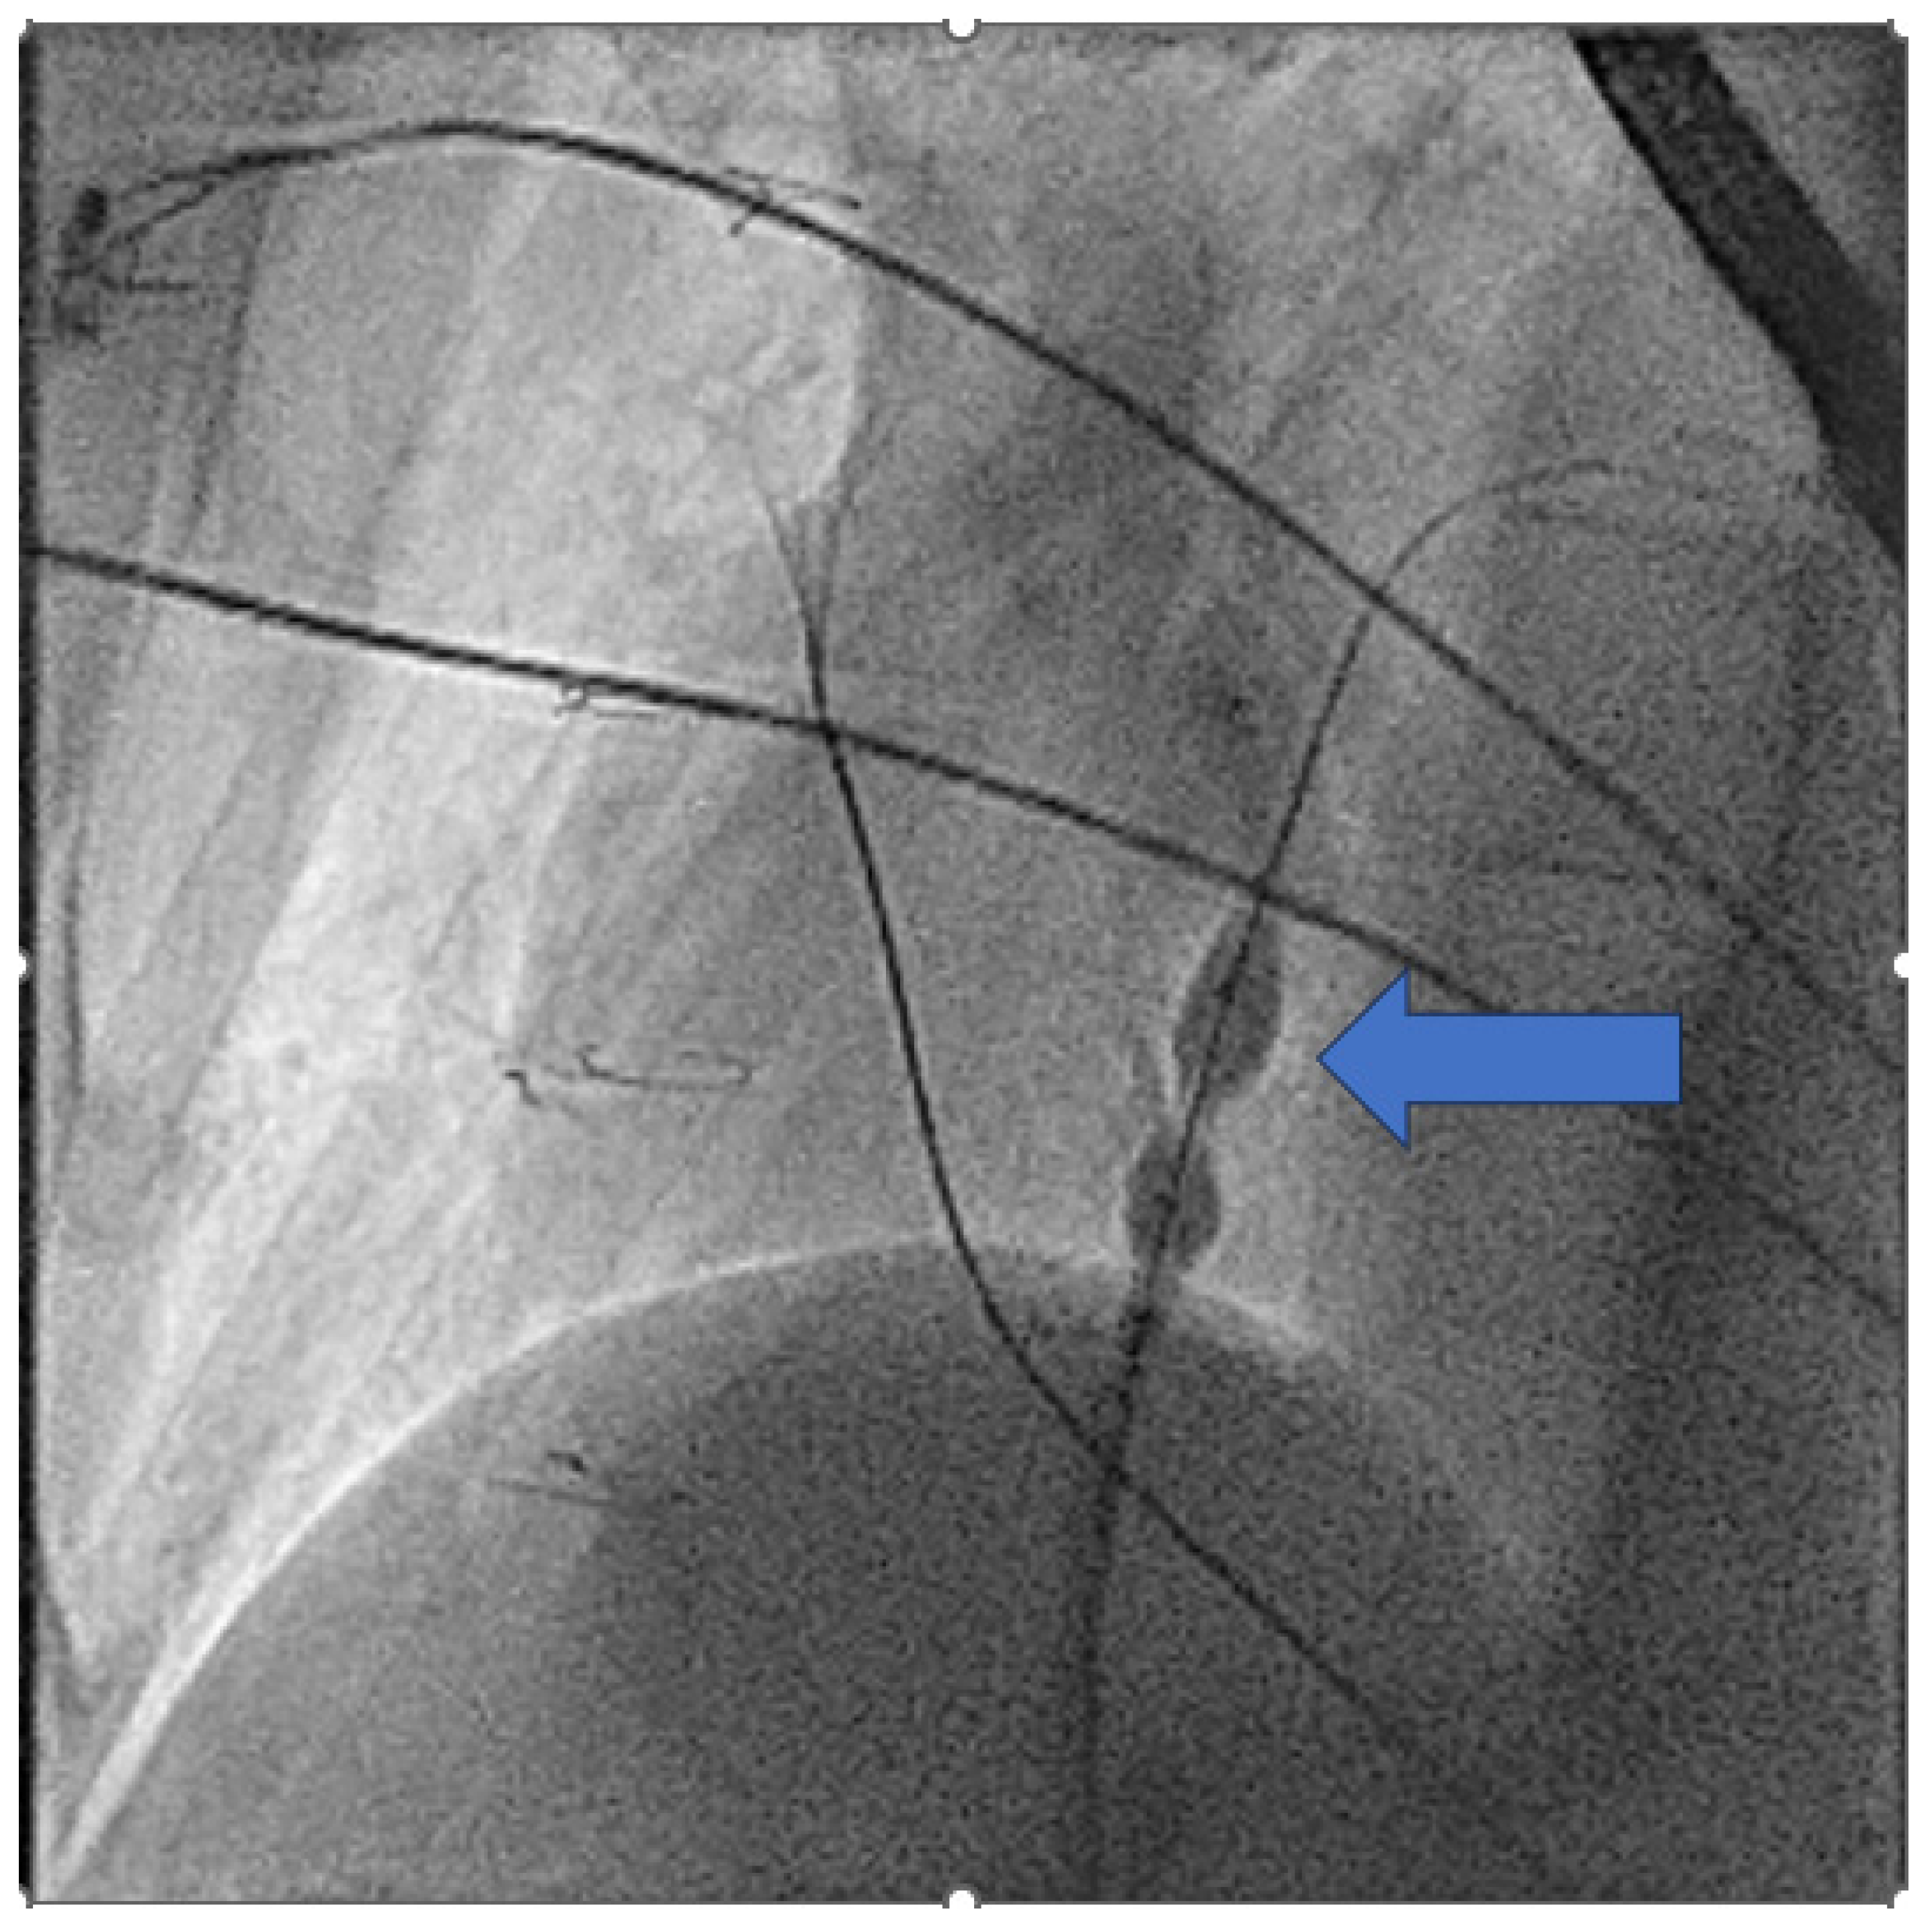

- Hayle, P.; Altayeb, F.; Hale, A.; Rao, A.; Ashrafi, R. Case report demonstrating novel approaches for leadless pacemaker implantation in the single ventricle heart. Eur. Heart J. Case Rep. 2025, 9, ytaf146. [Google Scholar] [CrossRef]

- Goulden, C.J.; Khanra, D.; Llewellyn, J.; Rao, A.; Evans, A.; Ashrafi, R. Novel approaches for leadless pacemaker implantation in the extra-cardiac Fontan cohort: Options to avoid leaded systems or epicardial pacing. J. Cardiovasc. Electrophysiol. 2023, 34, 2386–2392. [Google Scholar] [CrossRef]